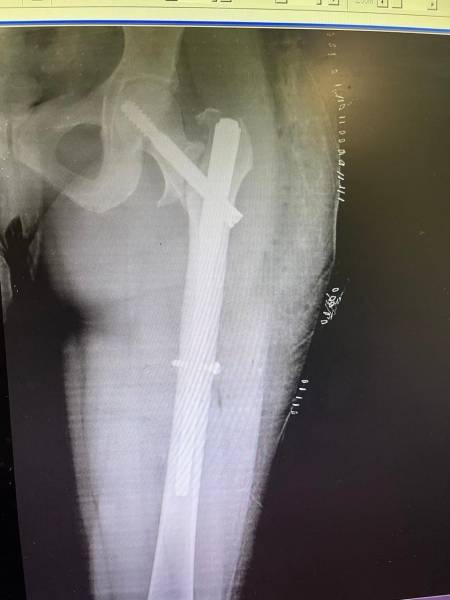

- إجراء عمليات جراحية معقدة و دقيقة في مجال العظام و المفاصل و الكسور و الإصابات ، رغم الضغط الكبير على المستشفى و أعداد المراجعين الكبيرة.

- تطبيق تقنيات جراحية حديثة و متقدمة، و ذلك في ظل التحديات التي يواجهها الفريق بسبب أعداد المرضى و المراجعين الكبيرة.